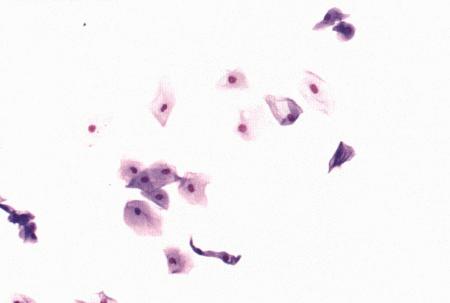

Вагинальная цитология

Повышение концентрации эстрадиола в период проэструса стимулирует деление клеток в базальных слоях вагинального эпителия, но затем концентрация эстрадиола, а соответственно и эндокринная поддержка образования нового, многослойного эпителия снижается, поэтому в образце обнаруживается больше мертвых ороговевших клеток. По мере развития проэструса снижается количество эпителиальных клеток, содержащих ядро. С начала до середины проэструса в вагинальных мазках обнаруживают повышенное содержание эритроцитов. Пик ороговения совпадает с началом повышения концентрации прогестерона; однако в начале эструса исследование не обнаруживает характерных особенностей, которые могли бы указывать на начало фертильного периода. Как правило, такой период наступает несколькими днями позже (табл. 1.1). Тем не менее вагинальная цитология остается популярным методом определения репродуктивного статуса суки из-за своей дешевизны, простоты и доступности. Для получения образца используют ватный тампон, предпочтительно небольшой, который вводят во влагалище и осторожно берут мазок. Полученные клетки помещают под микроскоп, а затем окрашивают контрастным (трихромом) или неконтрастным (например, препаратом Diff-Quik) веществом. При таком окрашивании мертвые кератинизированные клетки становятся оранжевыми, тогда как активные ядерные клетки, а также базальные и парабазальные эпителиальные клетки приобретают различные оттенки от голубого до зеленого.

Ближе к окончанию эструса вагинальные выделения претерпевают характерные изменения (снова выявляются эпителиальные клетки, содержащие ядро, и появляется большое количество лейкоцитов). Такая картина обычно наблюдается через 7–9 дней после пика ЛГ и известна как «вагинальный мазок метэструса». Изменению характера выделений предшествует переходный период, характеризующийся возрастающим количеством активных клеток и указывающий на окончание фертильного периода и эструса (табл. 1.1).

Вагинальная цитология весьма информативна в плане определения фазы эстрального цикла, однако значительные расхождения во времени появления основных признаков эструса по отношению к пику фертильности ограничивает применение указанной методики.

Фиг. 2.2.

Вагинальные выделения кошки (а). Выделения, типичные для фазы эструса. Большая часть клеток представляет собой безъядерные кератинизированные клетки или клетки с пикнотическим ядром. Присутствуют промежуточные клетки (b). Выделения, характерные для метэструса, — «течки», иногда наблюдаемой у кошек в конце эструса. Присутствуют поверхностные и промежуточные клетки, повышено содержание лейкоцитов. Этот короткий метэструс наблюдается в течение 24–48 часов (см. Приложение)